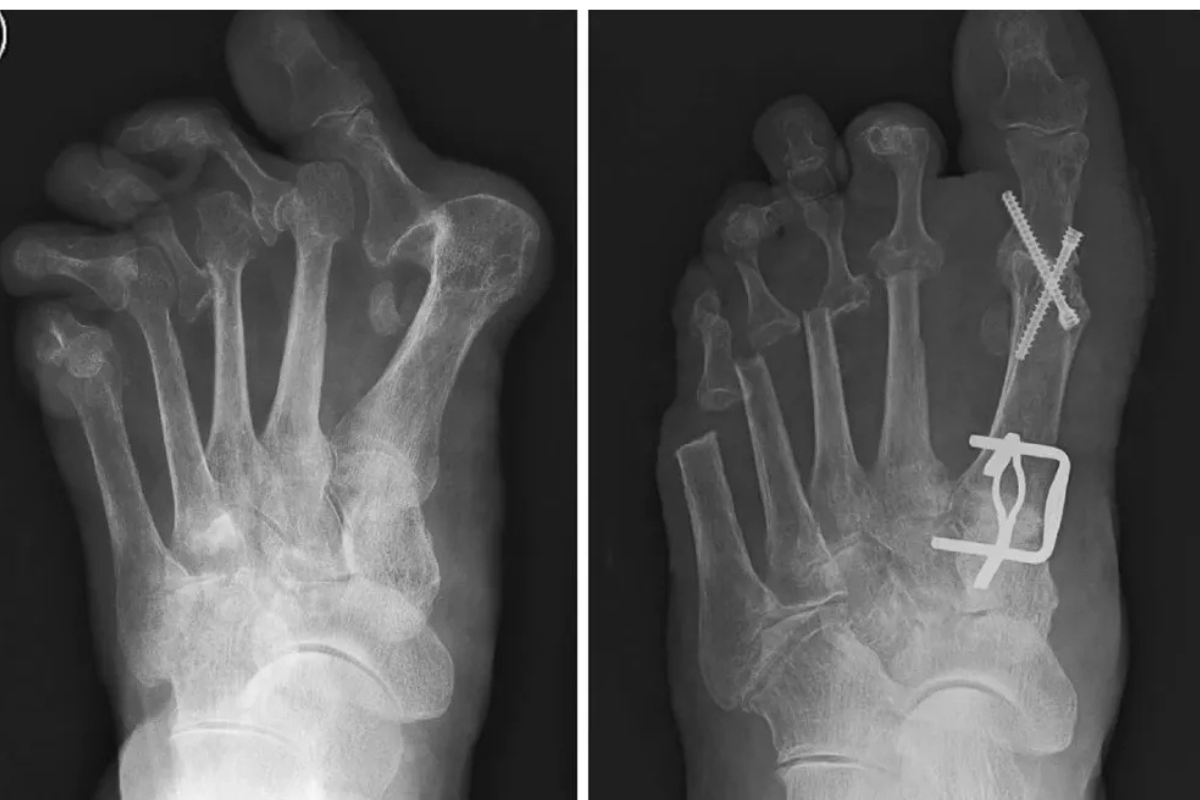

Since its founding Bobade Hospital has been providing its patients with the full medical care, encompassing outpatients services, is neurology, laboratory, imaging diagnostics and more.